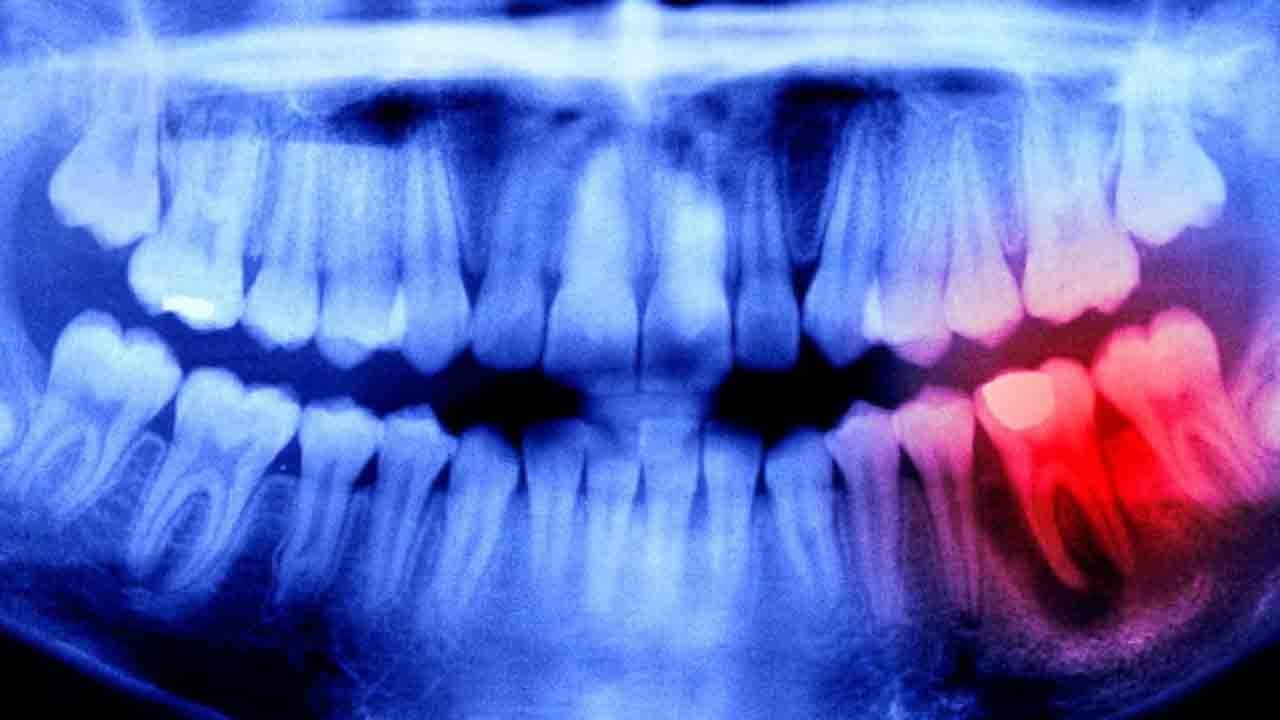

Dişler, yapıları gereğince kemiklerle aynıdırlar. Ancak kemiklerin aksine dişlerin kendini yenileme, kırılma hâlinde onarım gibi bir özellikleri yoktur. İşte Japon bilim insanları, geçmişten gelen bilgi birikimini de kullanarak bu duruma bir çözüm ürettiler. Bilim insanları, 2030 yılı itibarıyla ilacı genel kullanıma açacaklarına inanıyorlar.